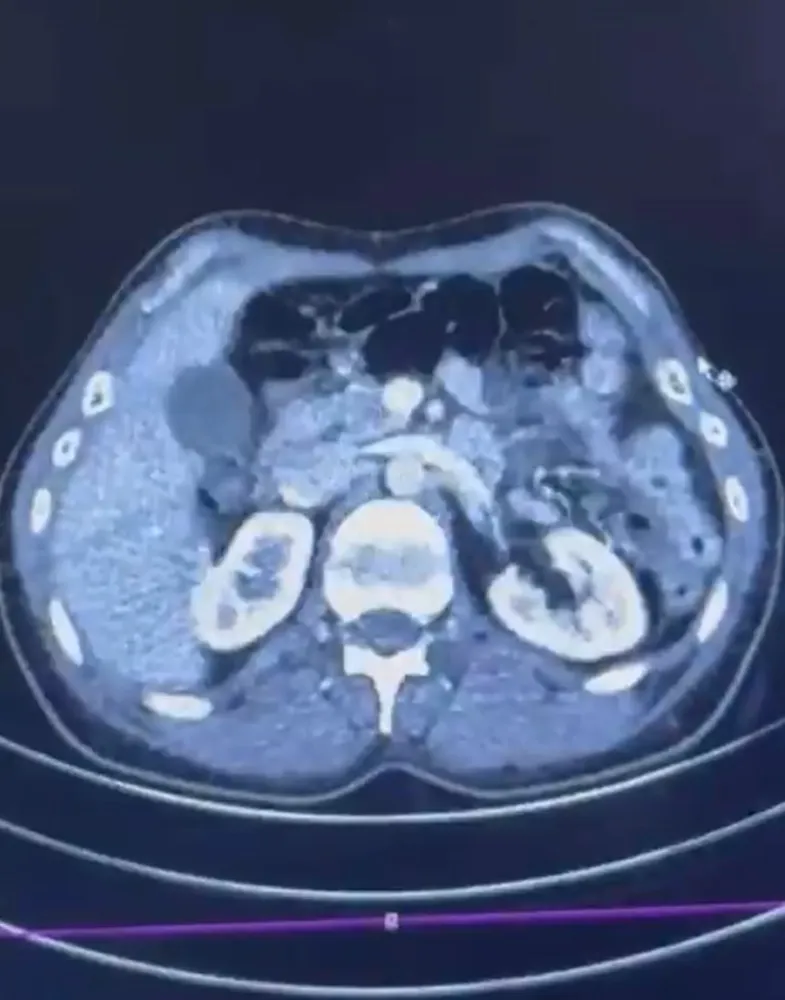

Düzenlenen operasyonda; S.C., R.B.C. ve G.M. yakalandı. S.C. ve R.B.C.'nin Kayseri Şehir Hastanesi'nde yapılan iç beden muayenelerinde, mide kısımlarında bulunduğu tespit edilen 50 adet kapsül şeklinde toplam 554 gram uyuşturucu madde ele geçirildi. Şüpheliler gözaltına alınarak haklarında 'Uyuşturucu Madde Ticareti Yapmak' işlem başlatıldı.